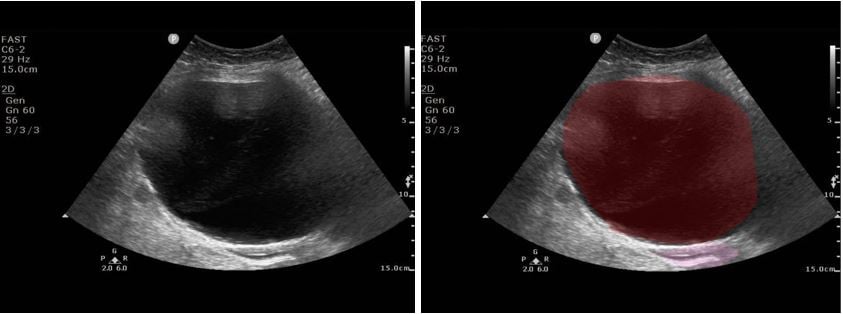

A 78-year-old female with a past medical history of recent CAD with NSTEMI and rectus sheath hematoma presented with severe abdominal pain via EMS. In transport, the highest heart rate was 35, and the lowest blood pressure was 93mmHg systolic. The patient had been discharged from rehabilitation four days prior to presentation. She reported mild pain at discharge that acutely worsened on the day of presentation. While the patient was being volume resuscitated, a RUSH exam was performed that showed severely reduced LVEF and a distended bladder. A foley was placed and minimal urine came out. The patient’s blood pressure and heart rate improved, and she was transported to the CT scanner, where a large pelvic hematoma was identified. The patient was taken for ex-lap and admitted to the surgical ICU.

Figure 3. Bladder Ultrasound. Red: Hematoma; Pink: Uterus